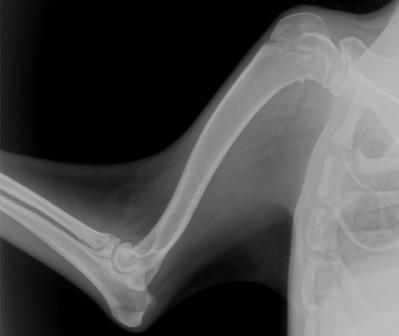

Рентгеновский снимок

• 2 стадия - дистрофическая. Покраснение исчезает, но припухлость сохраняется. Кожа в области поражения становится холодной, напряженной, приобретает синеватый оттенок. Тонус мышц повышается. Кожа и мышечная ткань постепенно атрофируются. На рентгеновском снимке возле костей видны характерные пятна.